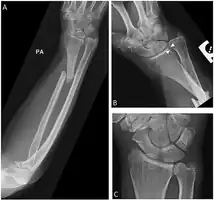

Galeazzi fracture

| Galeazzi fracture-dislocation | |

| Galeazzi fracture. Arrow points at the dislocated ulnar head | |

The Galeazzi fracture is a fracture of the distal third of the radius with dislocation of the distal radioulnar joint. It classically involves an isolated fracture of the junction of the distal third and middle third of the radius with associated subluxation or dislocation of the distal radio-ulnar joint; the injury disrupts the forearm axis joint.[1]

The dislocation of ulnar head in Galeazzi fracture dislocation may be dorsal (commoner) or volar (rare) depending on the mechanism of injury. If the fall is on the outstretched hand with forearm in pronation, the dislocation is dorsal, and if forearm is in supination at the time of injury, the dislocation is volar.[2]